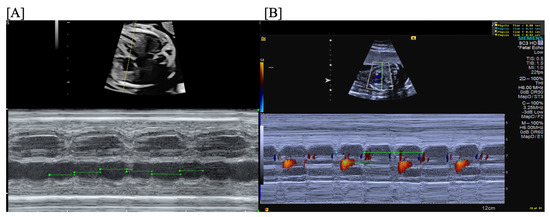

2. Types of Fetal Arrhythmias

3. Extrasystoles